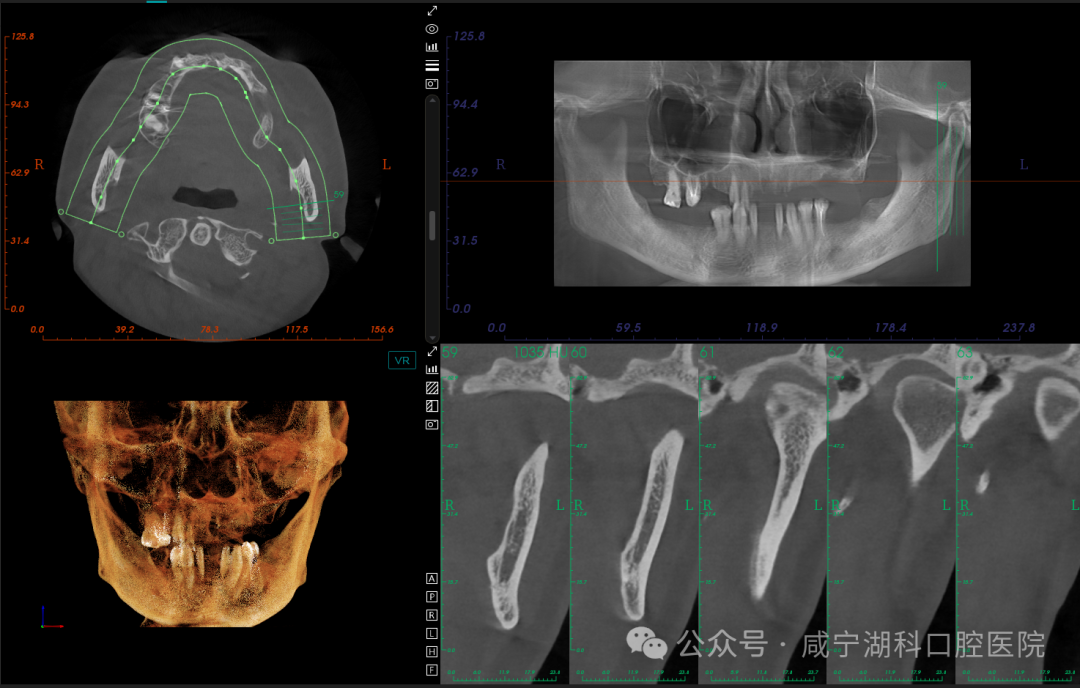

刘伟院长根据胡阿姨的牙齿情况,分析到上颌窦剩余骨量非常少,做种植有两种方式,一种是采用上颌窦外提升,需要大量植骨,要忍受大半年至一年的无牙期,而且要进行两次手术才能完成修复。第二种是穿翼种植,是一种新技术,目前咸宁掌握这项种植技术的医生很少,这项技术是拔完牙后即刻就进行穿翼种植,只用一次手术就能完成种植,当天就能戴牙,大大缩短修复时间,减少无牙痛苦。

拍摄口腔CT,进行专业分析

经过多方比较,1月25日,胡阿姨最终选择了刘伟院长为她进行穿翼种植,最终当天拔掉上颌两颗松动牙,保留了2颗大磨牙,植入5颗种植体,当天拔牙当天种当天戴固定牙。她说:“毕竟湖科口腔口碑很好,种植牙是很考验医生技术的手术,既然要做,就要找靠谱的、术后维护有保障的医院,技术过硬的医生。”